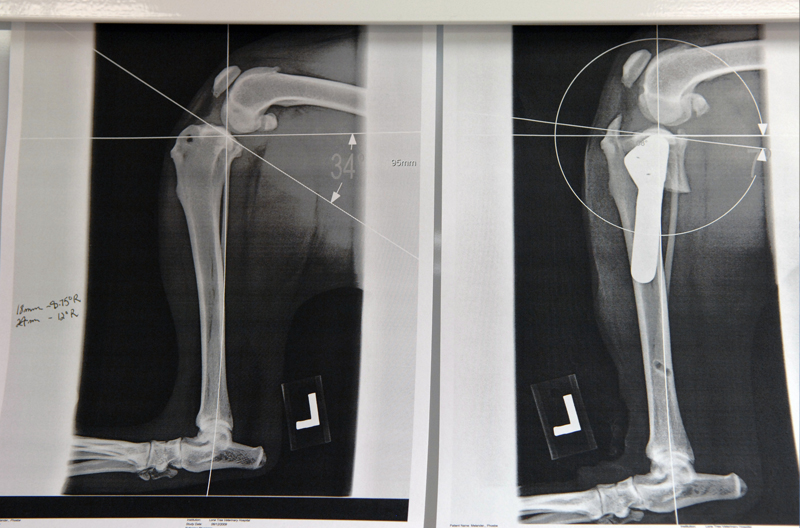

Before and after x-rays

X-rays showing before (left) and after (right) TPLO surgery.

We use an orthopedic examination and x-rays to determine whether or not a CCL is torn and to what extent. Once the diagnosis is established, we determine whether the TPLO procedure will provide the best surgical solution.

The Tibial Plateau Leveling Osteotomy (TPLO) is one of the most widely used procedures for repairing a torn CCL in dogs. Instead of just repairing a CCL tear and leaving it susceptible to re-injury, the TPLO corrects the underlying conformation problem of the knee by permanently removing the stress on the supporting ligaments. This greatly reduces the chance for ligament damage in the future. It also allows the pet to resume a normal, active life.